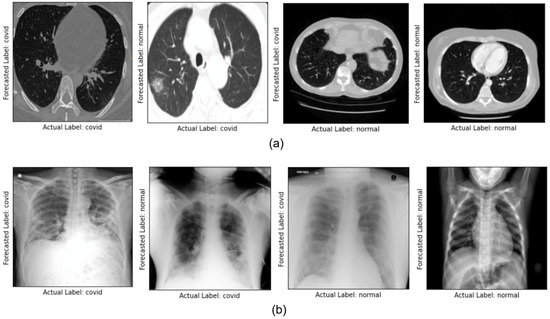

3. Methodology

4. Result and Discussion